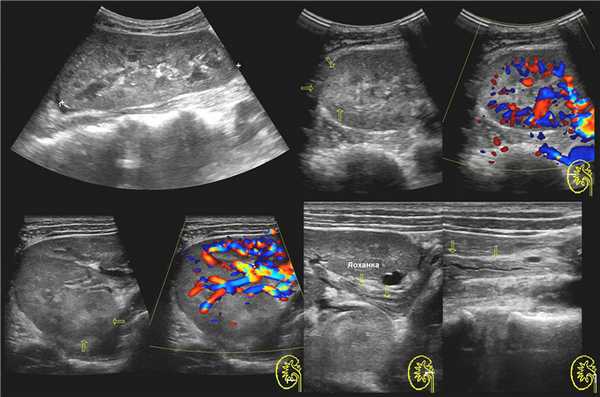

На УЗИ в мочевом пузыре или в уретре определяется анэхогенное образование, округлой формы, с четким и ровным контуром; соответствующий мочеточник обычно заметно расширен; может присутствовать гидронефроз верхней части удвоенной почки. Уретероцеле определяют как внутрипузырные (полностью внутри мочевого пузыря) или внепузырные (некоторая часть постоянно расположена в шейке мочевого пузыря или в уретре).

Рисунок. У новорожденного на УЗИ почек определяется гидронефроз (1) и расширенный мочеточник (2) справа. В мочевом пузыре двустороннее уретероцеле (3). При исследовании левой почки структурных изменений не выявлено.

Рисунок. На УЗИ определяется удвоенная чашечно-лоханочная система, расширена лоханка верхнего сегмента (1) и мочеточник на всем протяжение (2, 3), в мочевом пузыре уретроцеле (4). Полное или неполное удвоение чашечно-лоханочной системы возможно увидеть с помощью КТ-урографии.

Рисунок. Дистальный отдел мочеточника расширен, в мочевом пузыре анэхогенное образование с тонким и ровным контуром — уретероцеле.

Рисунок. Двустороннее уретероцеле на УЗИ: в режиме ЦДК из верхушек уретероцеле определяется выброс мочи.

Рисунок. На УЗИ в уретероцеле определяется гиперэхогенная структура с акустической тенью — камень. Уретероцеле может являться одним из факторов, способствующих камнеообразованию.